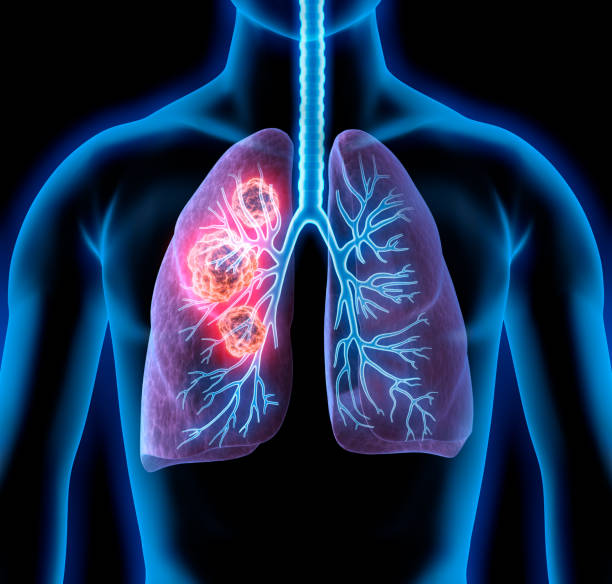

폐암은 초기에는 증상이 미미하거나 없을 수 있습니다. 그러나 조기에 발견하고 진단받으면 치료의 성공률이 훨씬 높아집니다. 초기에 폐암을 발견하면 조기 치료를 시작하여 종양의 성장과 전이를 제한할 수 있습니다. 뿐만 아니라, 치료에 있어 다양한 치료 방법을 활용할 수 있어 폐암 초기 증상을 잘 알고 있는 것이 중요합니다.